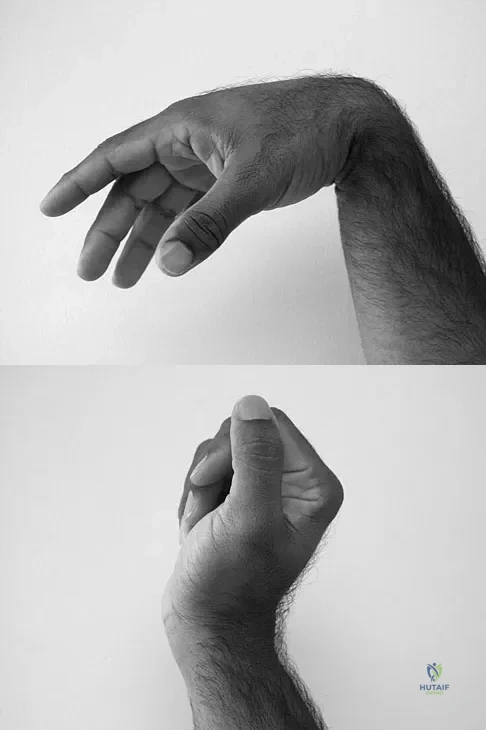

Question 49

A 35-year-old man sustained a 1-inch stab incision in his proximal forearm while trying to use a screwdriver 2 weeks ago. The laceration was routinely closed, and no problems about the incision site were noted. He now reports that he has been unable to straighten his fingers or thumb completely since the injury. Clinical photographs shown in Figures 30a and 30b show the man passively flexing the wrist. What is the most appropriate management?

Explanation